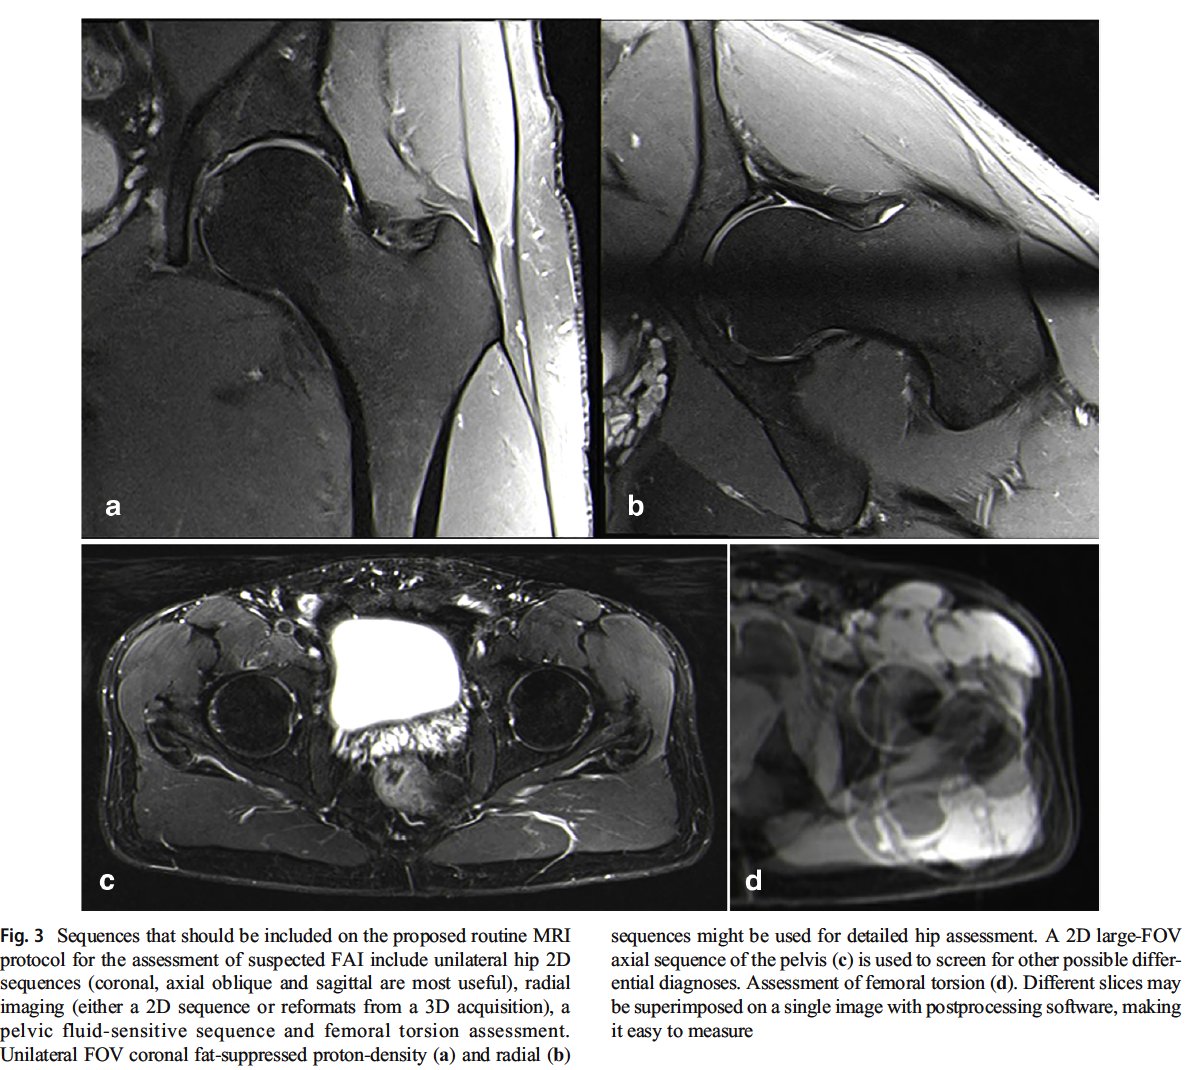

FAI week! Parts 2 & 3 of Lisbon "trilogy" on FAI imaging Control Hip Hype!

Part 2: https://pubmed.ncbi.nlm.nih.gov/33411052/

Part 3: https://pubmed.ncbi.nlm.nih.gov/33411053/